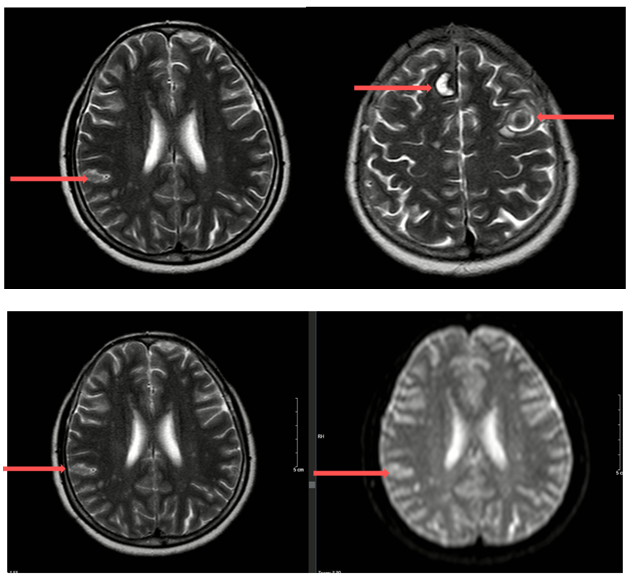

MRI sọ não (05/2024):

Hình 1: Hình ảnh các khối, nốt tổn thương có chảy máu thùy trán phải, góc cầu tiểu não trái, các nốt chảy máu thùy trán trái, thùy thái dương – thùy chẩm phải – theo dõi các tổn thương thứ phát.